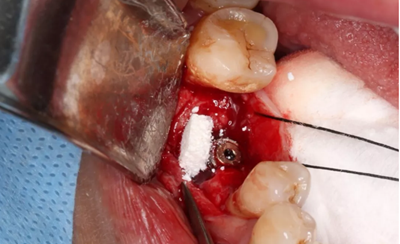

使用直徑3mm的環(huán)形取骨鉆切取長(zhǎng)約9mm的柱狀骨標(biāo)本,用于組織學(xué)和顯微影像檢查

(攝于2017年4月14日)

由于取骨致窩洞較大,加之缺牙間隙大,只好選擇植入5mm直徑種植體;種植備洞完成后,頰側(cè)骨壁厚度僅約1mm。